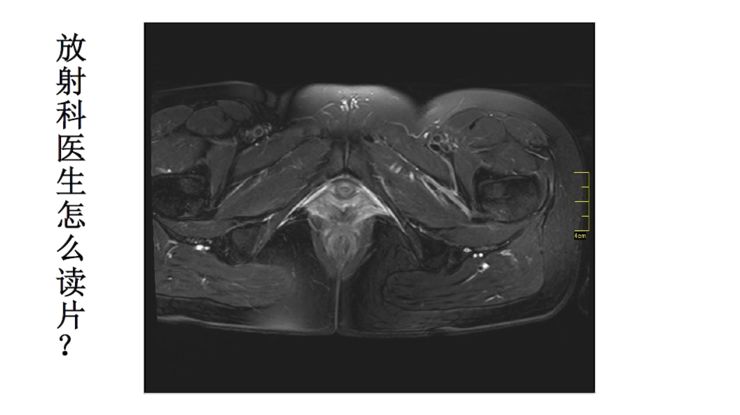

所以放射科医生是怎么读片?就是一层一层地观察图像。举个例子,这是一个T2加权像序列,可以看到膀胱,尿液是亮的,然后能看到子宫,然后能看到双侧卵巢,接着是宫颈,宫颈再往下一层一层延续下去就是阴道。